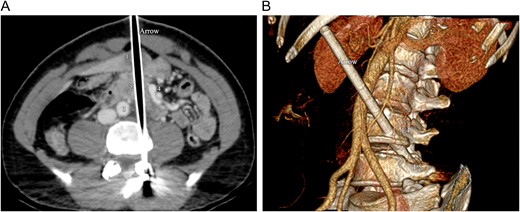

Intravenous contrast-enhanced CT of the abdomen. (A) Axial CT image shows the arrow, tracking through the liver (1), the pancreas (2) and the duodenum, between the aorta (3) and the superior mesenteric vessels (4). (B) 3D volume rendering CT reformation shows the oblique trajectory of the arrow, between the aorta (1) and the superior mesenteric artery (2). The arrow passes through the lateral aspect of the fourth vertebral lumbar body (L4) and ends into the left pedicle of the fifth lumbar vertebra (L5).